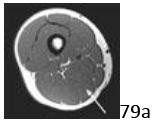

38a Figure 38a shows the cross-sectional anatomy of the proximal thigh. What structure is indicated by the arrow?

DISCUSSION: In Figure 38b, the arrow marks the adductor longus, which lies just deep to the superficial femoral artery. The adductor magnus is the larger, more posterior muscle on this

cross-sectional image. The adductor brevis is located between the adductor longus and magnus, deep to the deep femoral vessels. The sartorius is more superficial and covers the superficial femoral vessels. The gracilis is medial and more superficial. The Preferred Response # 38 is 2.